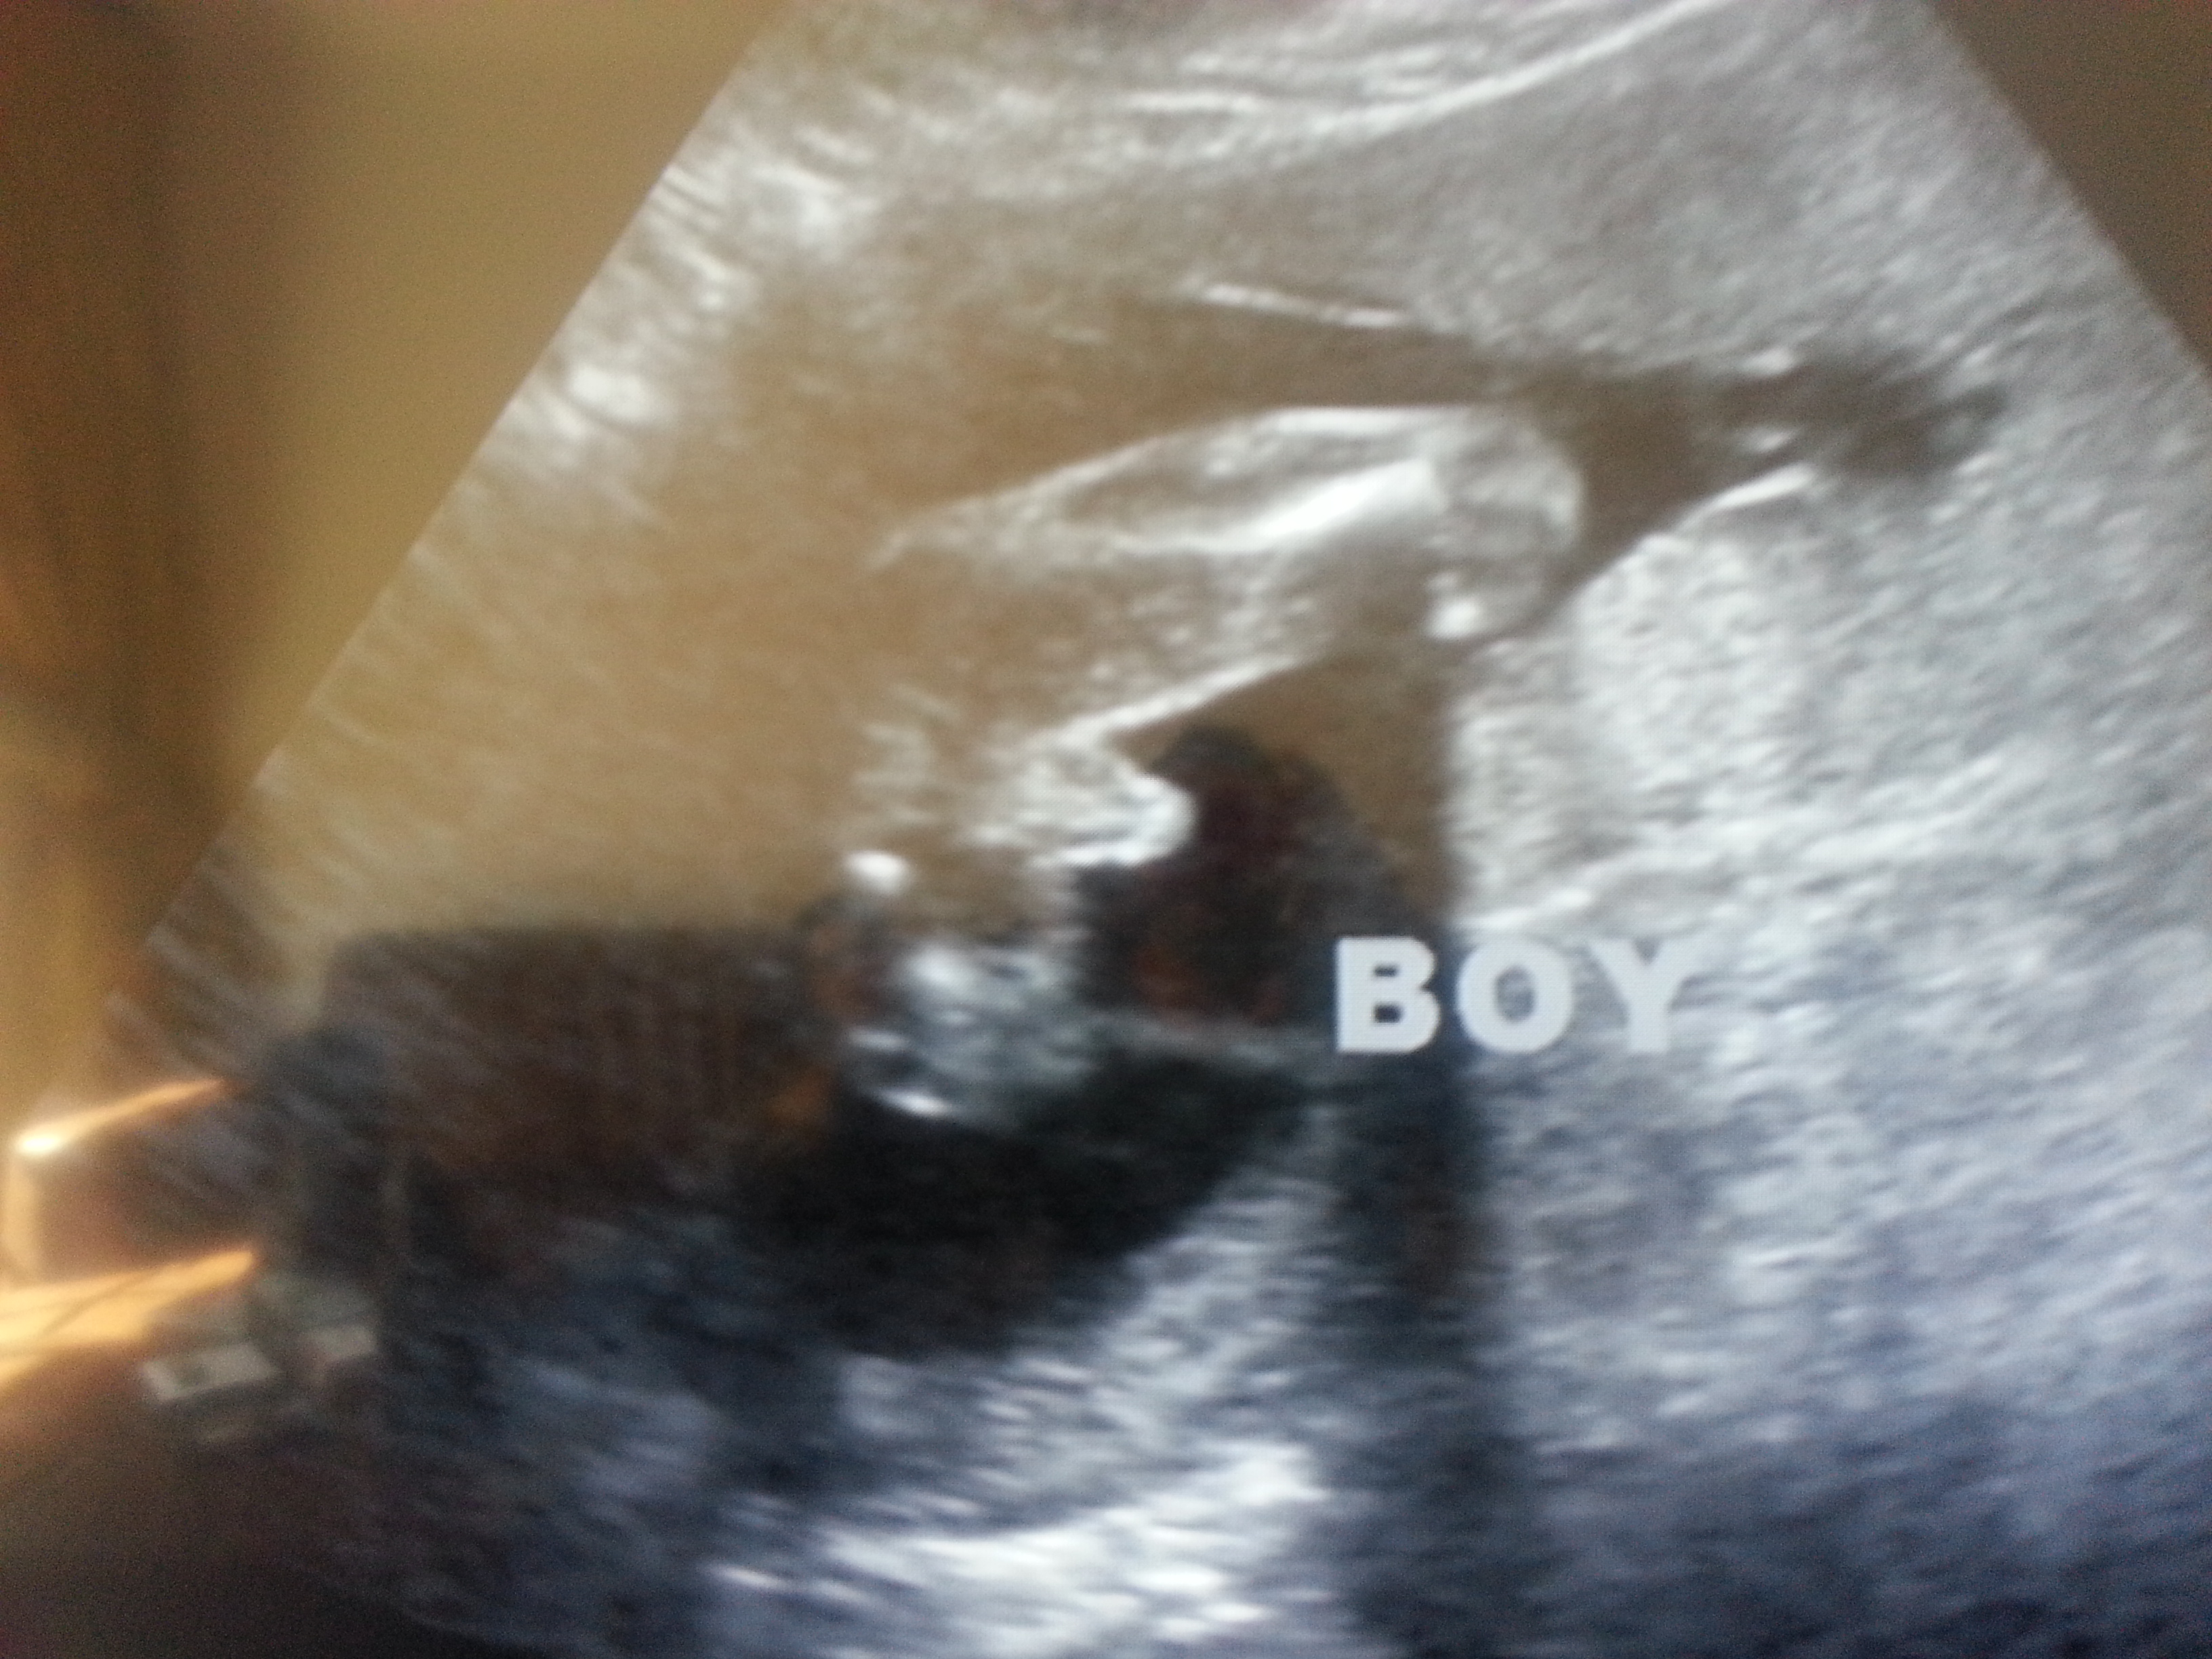

Attachment 253001Attachment 25299st tech said swollen female parts at 19 weeks. at 22 weeks secnd tech says definite boy

I would agree with the tech from your 22 week scan, my eldest boys potty shot was very similar.

Definitely boy.

For sure boy on both images !

Thanks guys. you think its possible at 19 weeks the scrotum was not fully developed and that's why the tech maybe thought swollen girl parts?

All boy :) To be honest I think the tech was having a bad day to have guessed girl off of the top picture??:)

I think the 19 week tech just wasn't very good at guessing gender because that 19 week scan does NOT look like a girl! :bigsmile:

I would say 99.9999% boy yes - girls don't have a protrusion like that at 22 weeks from what I know.